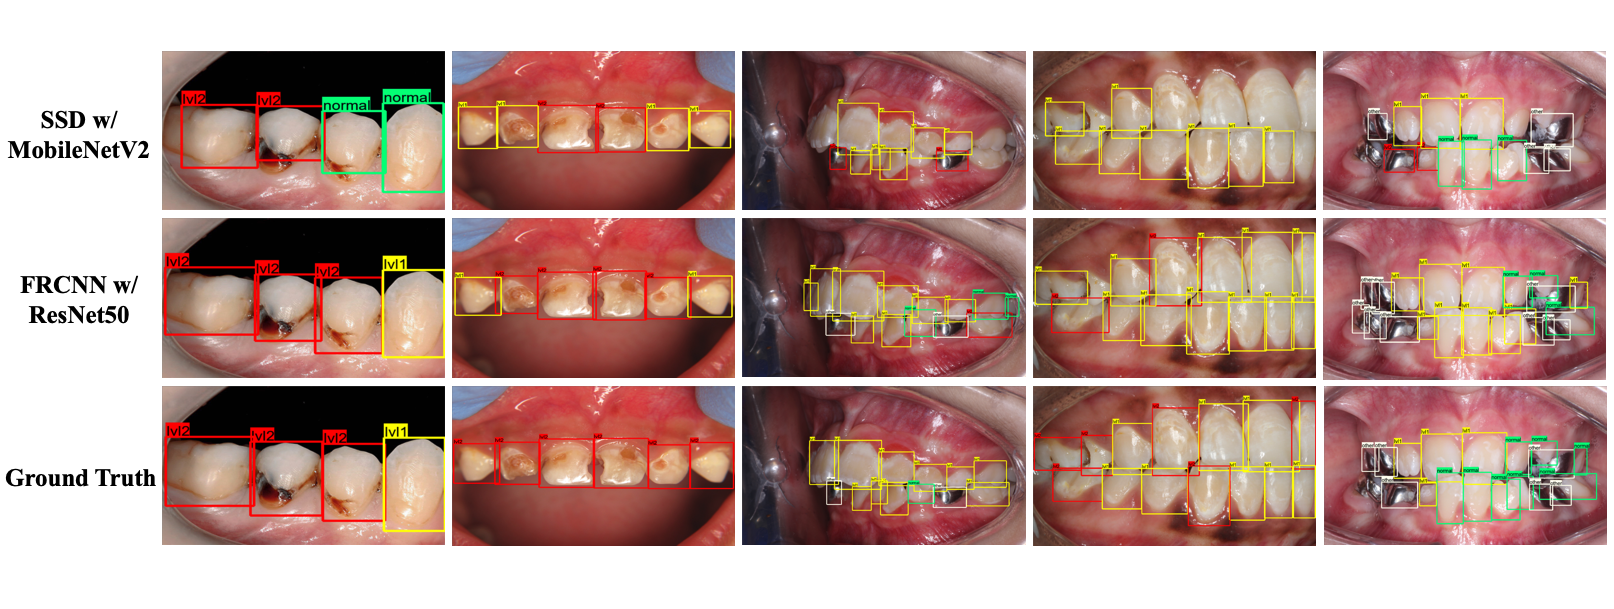

Refer to caption

Figure 4: Qualitative comparison between the cavity detection results by SSD and Faster R-CNN. Green boxes denote normal teeth; yellow boxes denote level 1 cavity; red boxes denote level 2 cavity; and white boxes denote human-imposed oral devices.

3.2.1 Qualitative Comparison

Fig. 4 shows the representative qualitative detection result comparison on the test set. We choose the images containing a wide range of teeth categories to visualize the models’ performance on all categories. It is clear that both models are able to correctly detect and classify most of the teeth in each image. We find the Faster R-CNN model performs significantly better than the SSD model; it successfully locates almost all the teeth and the misclassified teeth are sometimes those that are ambiguous in terms of severity levels. This is possible due to the different lighting conditions of the images. For example, the white spots in the signal level1 cavity class can be caused by flashlight from the camera. We observe that the SSD model sometimes cannot detect all the teeth in an image when the number of teeth is large. However, it also shows the capability of detecting most teeth that contain caries.